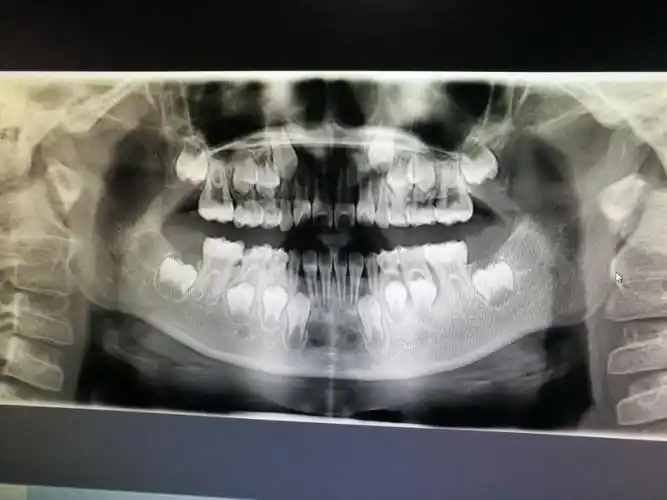

牙齿ct怎么看全景? - 知乎

牙齿ct照

口腔ct让你的牙齿更加健康美丽

术前ct